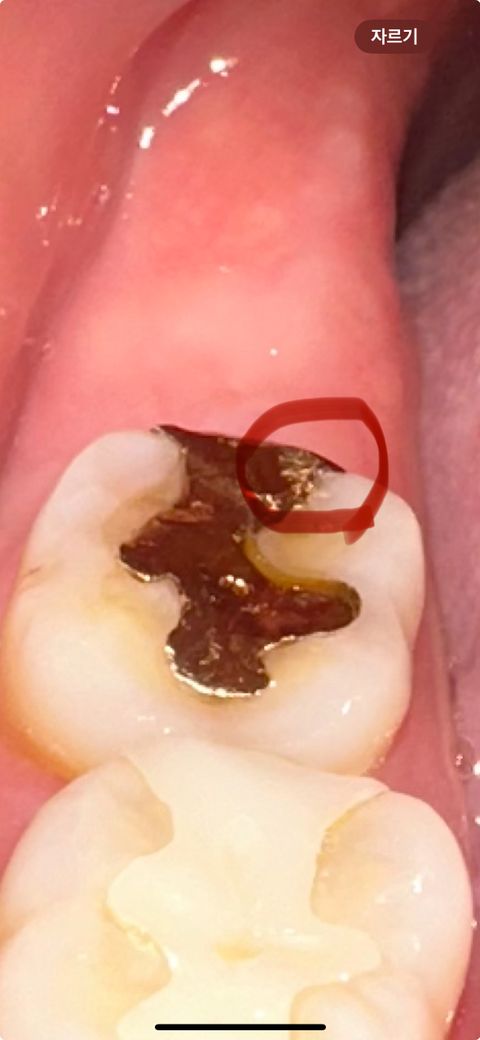

금이 벗겨진것처럼 보여요 큰 문제가 될까요?

원래 색이 저러지 않았는데 오늘 보니 저렇게 벗겨진것처럼 연하게 보여요 혹시 벗겨지기라도 한걸까요? ㅠㅠ 그냥 놔두면 문제가될까요? 시리거아 아프거나 불편한건 없습니다 무조건 보철물 교체 해야하나요?

• 1번 째 사진

• 골드가 일부 마모된 것으로 보여지며 벗겨진 것은 아닐 겁니다. 물론 정확한 것은 치과를 방문하여 해당 부위에 공간이 있는지 판단을 받아보는 것이 좋습니다. 계속해서 궁금증이 심하다면 가까운 치과 방문 후 평가를 한 번 받아보시길 바랍니다.

• 안녕하세요 치과의사 김철진입니다. 저정도 벗겨진건 크게 문제가 되진 않을것같습니다. 치아가 교모되서 그런거니 너무 걱정하지마세요.

• 금과 같은 보철물은 계속 사용하다보면 약간씩 마모가 됩니다. 마모가 되었다고 교체할 필요는 없으며

추후 문제가 생기면 바꾸면 됩니다.

• 쓰다보니 약간 금 인레이 보철물이 마모가된 것 같습니다 떨어지거나 벗겨진 것은 아니니 걱정하지 않으셔도 됩니다만 치과가서 체크는 해보실 수 있습니다